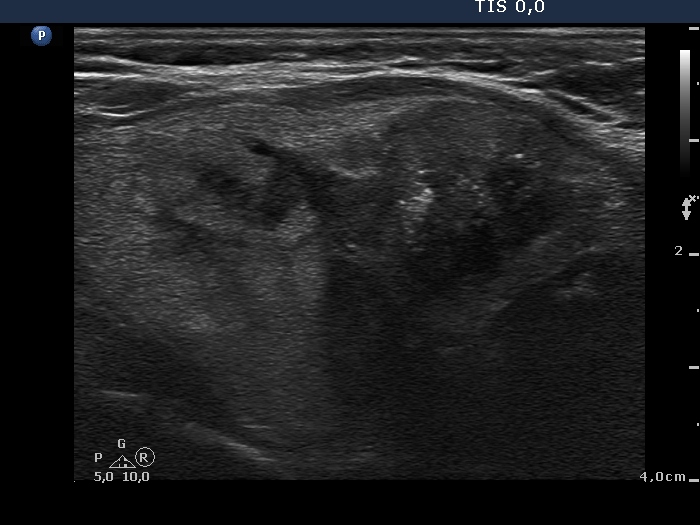

Medullary carcinoma (histological diagnosis)

The tumor has hyperechogenic granules and a larger echonormal irregularly shaped patch which corresponds to amyloid deposit. Note the dorsal acoustic shadowing.